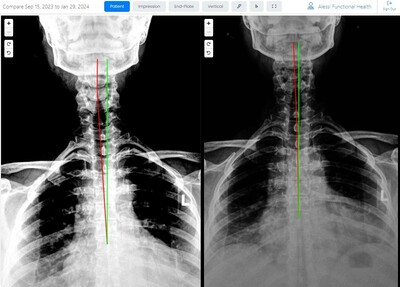

Results You Can See... and Feel!